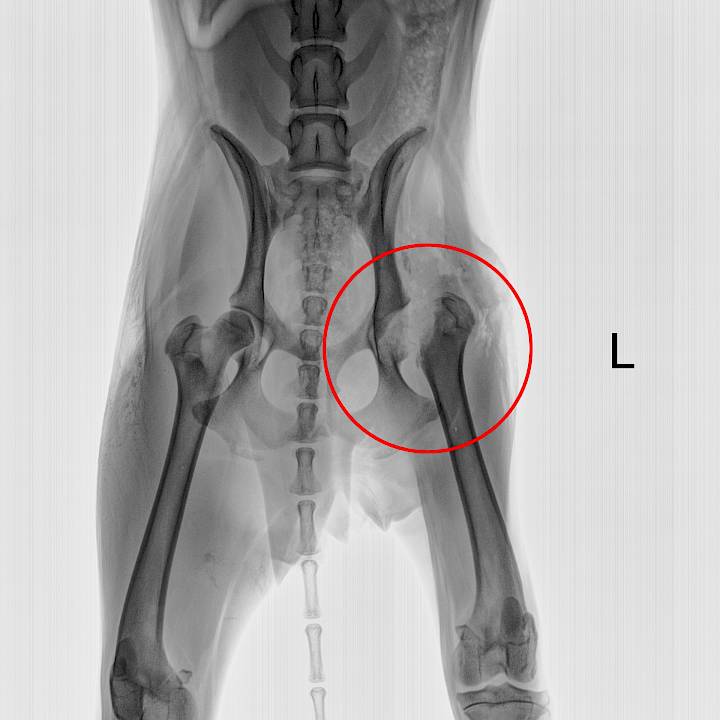

ซูกัสเป็นสุนัขที่แสนจะมีชีวิตชีวา เธอถูกรถชนจนได้รับบาดเจ็บ แต่โชคดีที่มีพลเมืองดีพบเห็นและนำเธอมารับการรักษาที่มูลนิธิของเรา เธอได้รับบาดเจ็บที่ขา ต้องเข้ารับการผ่าตัด และใช้ระยะเวลานานในการฟื้นฟูและกายภาพบำบัด หลังจากผ่าตัดได้ไม่นาน ซูกัสก็กลับมามีแรงอีกครั้งและพร้อมที่จะสนุกสนานกับชีวิตจนลืมไปว่าขาของเธอนั้นยังไม่หายดี